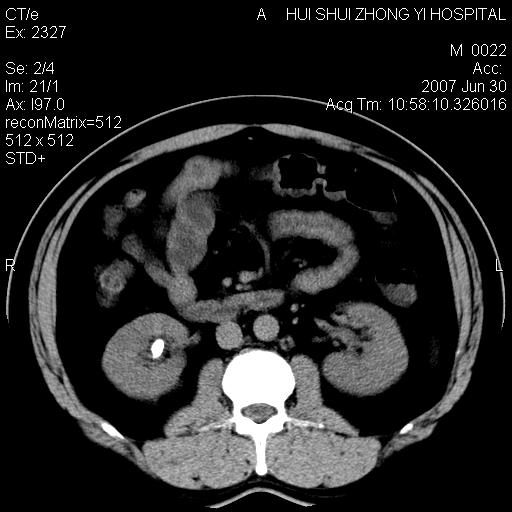

男,44岁,体检。

双肾结石

双侧肾盂、输尿管内结石,双侧肾脏轮廓呈波浪状,可能以前有过感染的

肝右叶密度减低区?

支持双肾结石,肝右叶低密度影为胆囊部分容积效应。

肝右叶低密度影为胆囊部分容积效应?为什么s43.0层面下来不见胆囊影,而是相隔了一层才见胆囊影。这是按我们扫描的顺序发的,但是是追加扫描的。

病人呼吸动了,第四层应该在第五\\六层之间。肝右叶低密度影为胆囊部分容积效应。双肾结石。